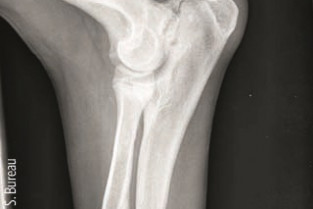

- Réaliser un bon cliché radiographique et l'interpréter

- Diagnostiquer et traiter la dysplasie du coude